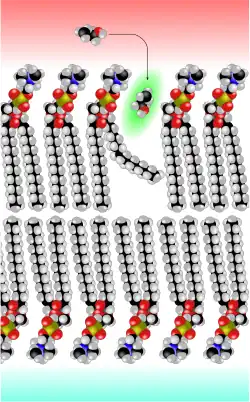

Der Göttinger Biophysiker Hermann Träuble entwickelte 1971 eine Theorie über den Transport von kleinen Molekülen durch die Zellmembran. Danach sind kleine, zwischen den Fettsäureketten der Lipiddoppelschichten befindliche Hohlräume für den diffusen Transport verantwortlich. Die Hohlräume entstehen durch Übergänge der anti- zur gauche-Konformation (trans-gauche-trans Kinks) in den Fettsäureresten der Phospholipide der Zellmembran. Zwischen diesen Konformationsübergängen liegen nur sehr niedrige Energieschwellen. Die Kinks (engl. kink ‚Knick‘) sind beweglich und wandern mit dem zu transportierenden Molekül durch die Membran.[104][105][106][107] Träubles Theorie wurde 1974 von Anna und Joachim Seelig NMR-spektroskopisch bestätigt.[108][109]